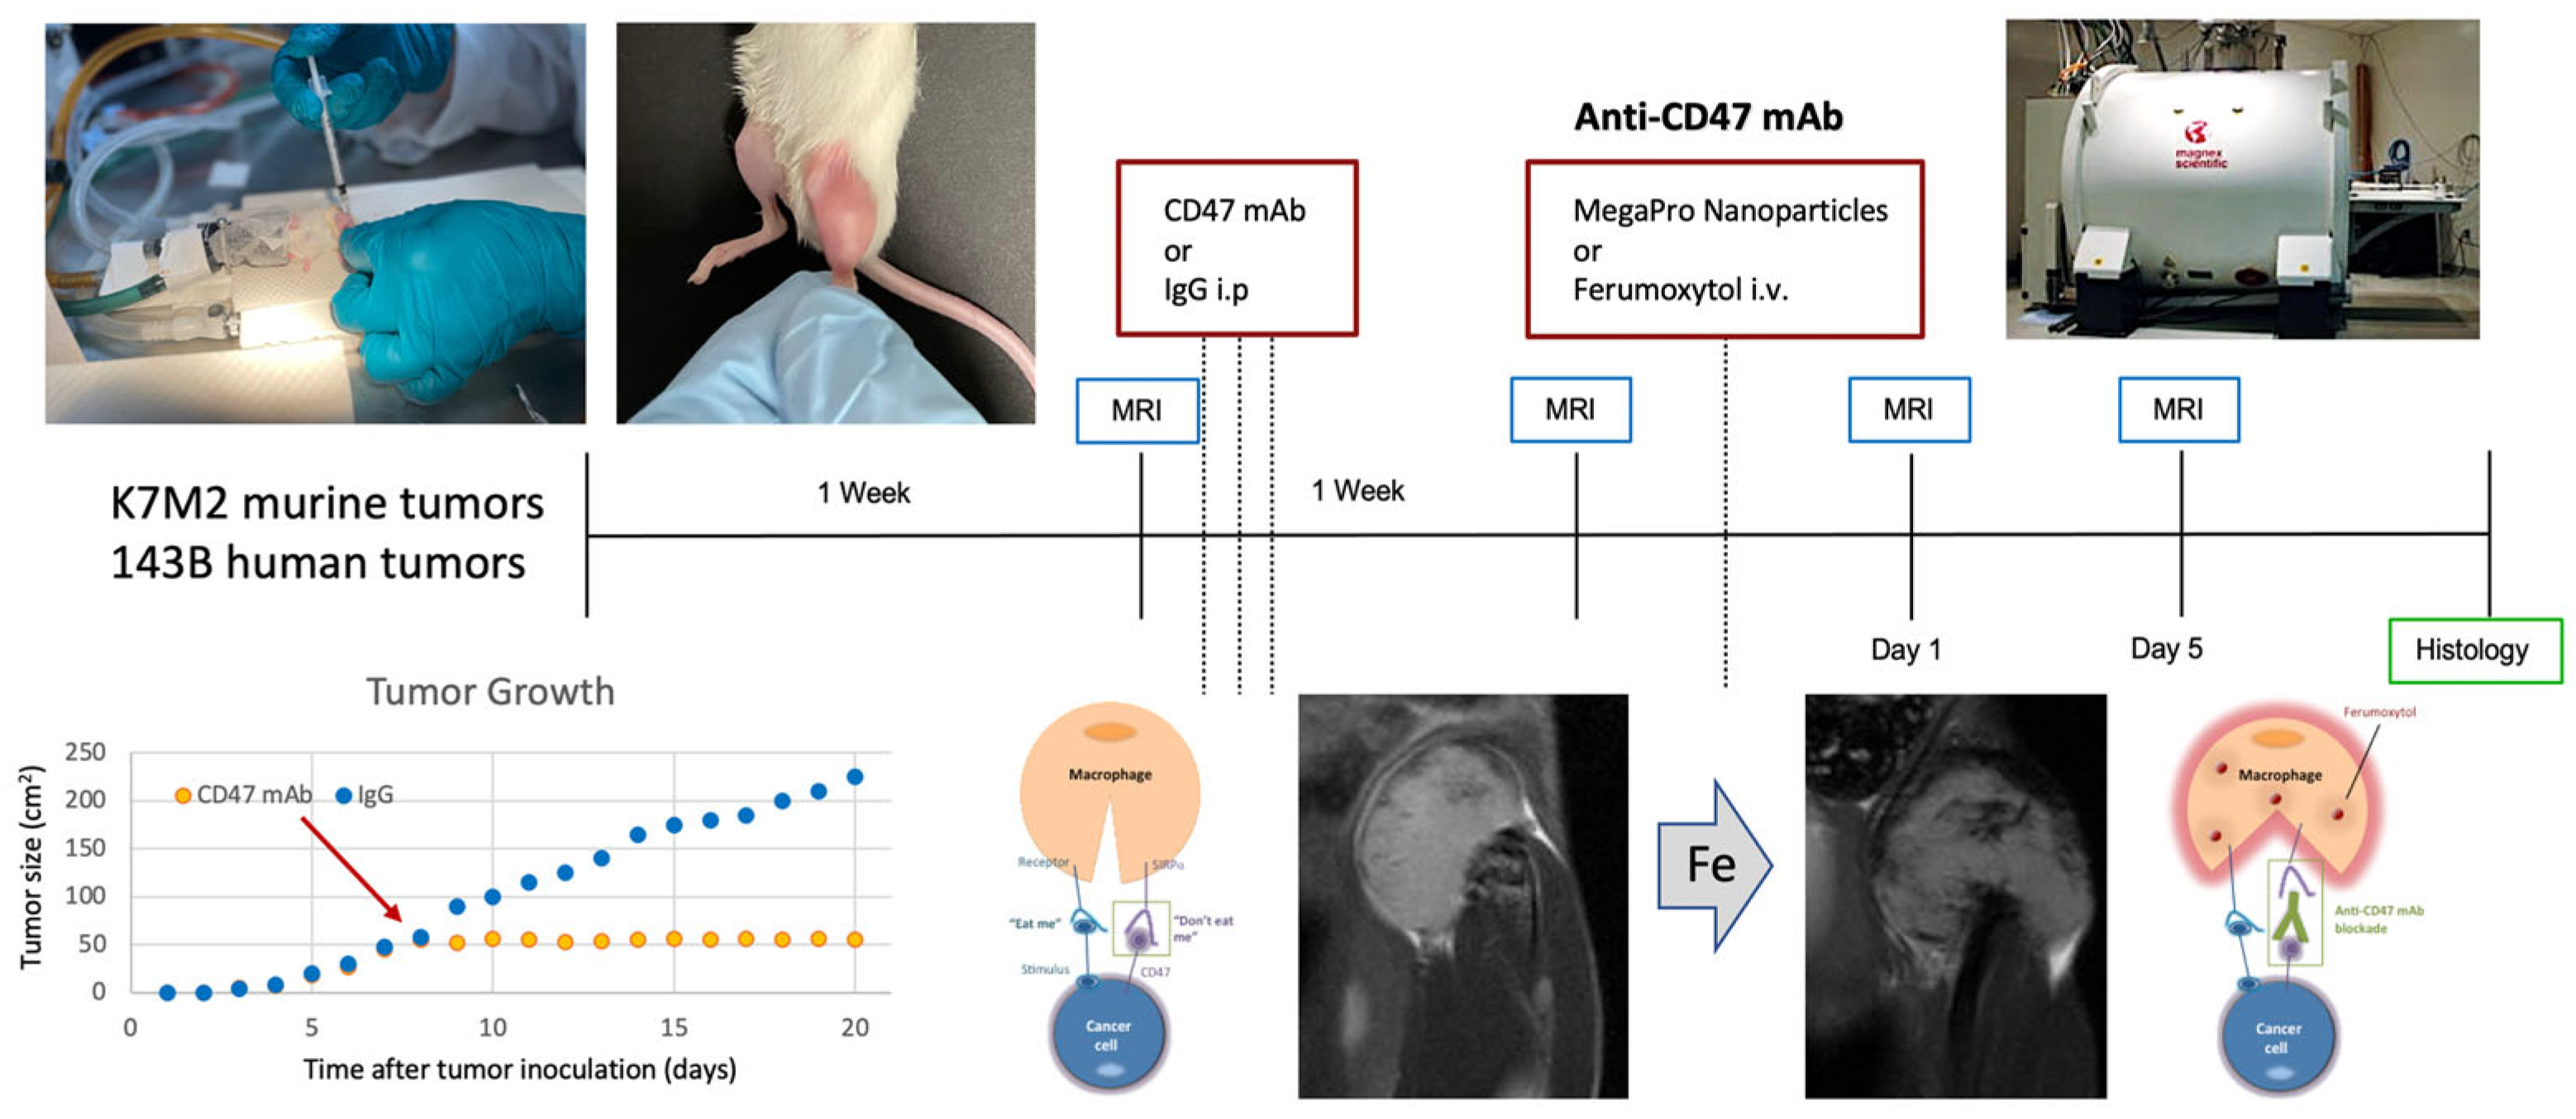

2.4. Stanford University Co-Clinical Research for Imaging Tumor-Associated Macrophages